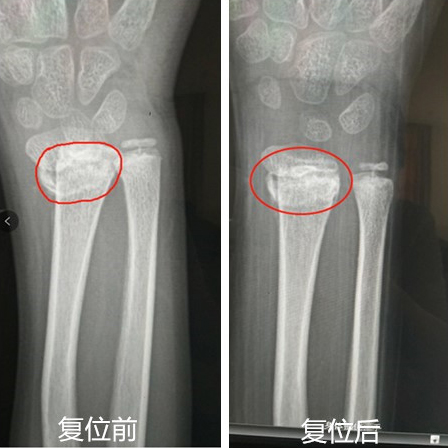

人民网重庆1月8日电 “本来以为复位后就好了,没想到过了一段时间再次错位,还越来越严重,当地医院都说时间拖太久,需要做手术,听说陈主任是骨科方面的老医生,我们就立马从璧山找来了”。家住重庆市璧山区的11岁男孩,去年暑假在和小伙伴玩耍时,不小心滑倒摔伤,经过检查,桡骨远端骨骺骨折严重错位,随即在当地医院进行了复位,但效果不佳,骨折在恢复期间又错位了。

“现在复位存在三个难点,一是不能破坏孩子骨骺线,影响孩子正常生长,所以不能进行手术治疗;二是错位的骨骺很薄,移位很严重,复位困难;第三是距骨折已经过了21天,错过了正骨复位的比较好时机。”陈国富医生检查后说,由于小孩生长发育快,错位的骨头正处于胡乱生长,需要重新掰断骨骼再正确复位,难度较大。经过综合评估,决定运用正骨手法为孩子接骨。

看到孩子的手在医生的治疗中,仅用了5秒钟,即成功复位,且DR摄片显示骨折处对位对线良好。孩子妈妈对治疗效果非常满意。